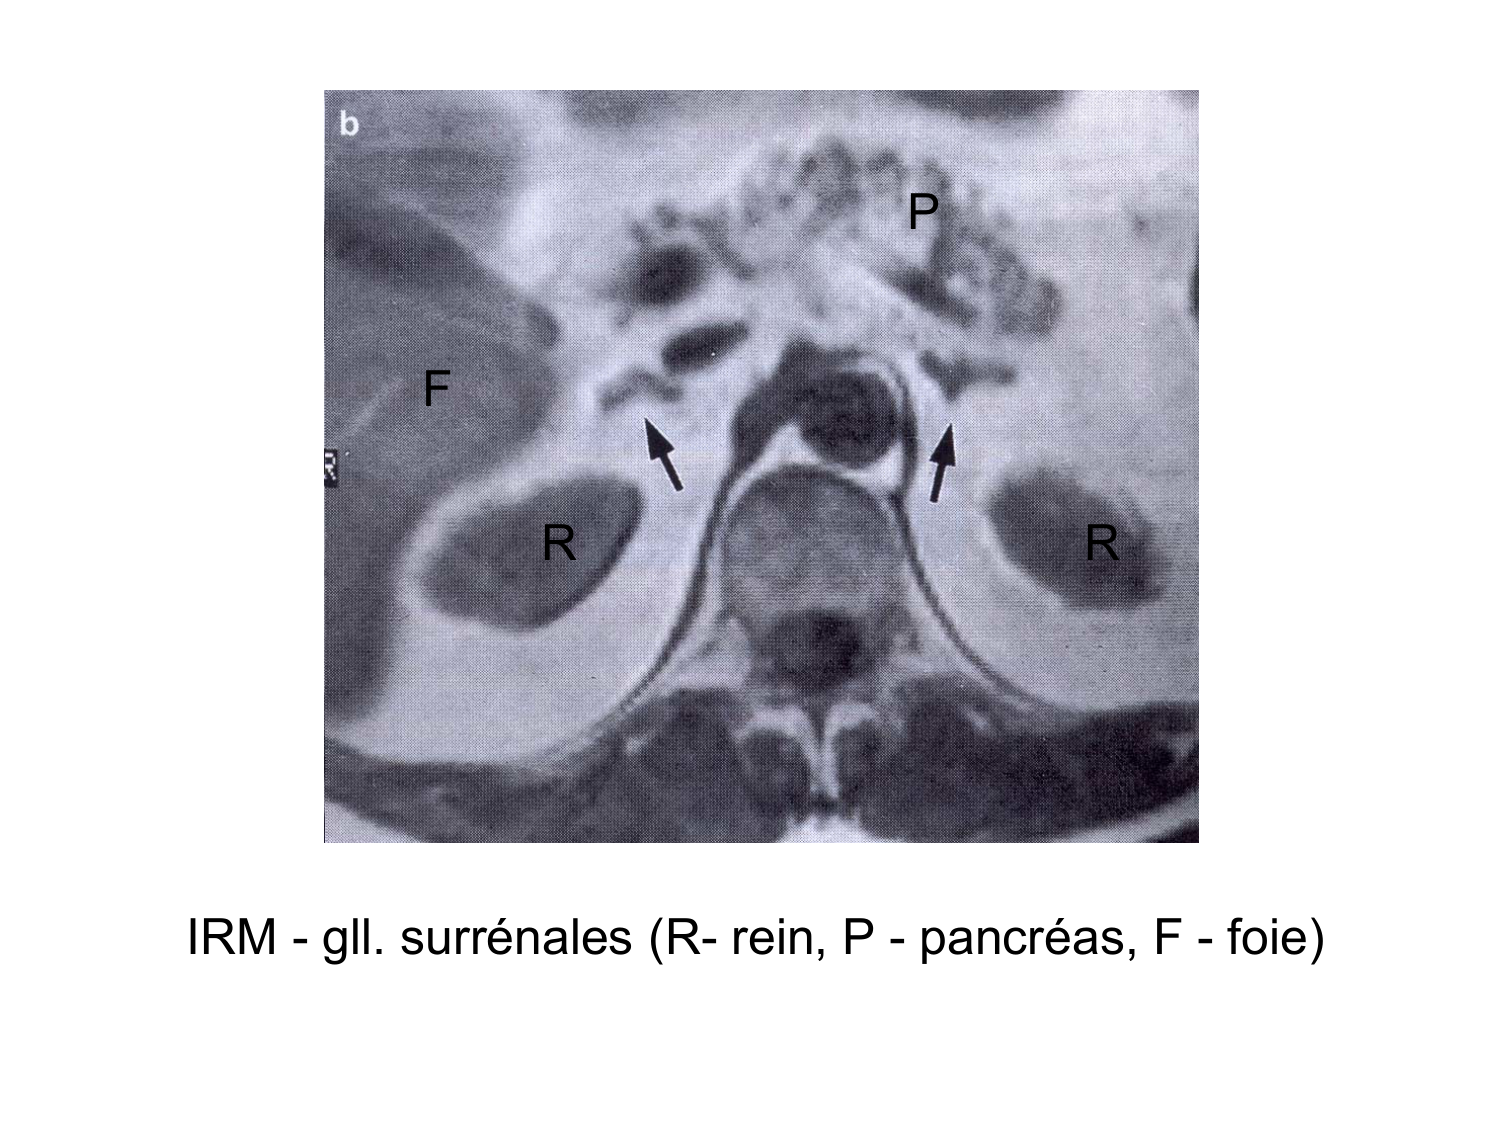

08.21 · Anatomie du système endocrinien2

Anatomie du système endocrinien2

Bases de l'anatomie · 92 pages · 12 sections